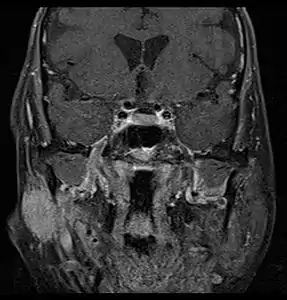

MRI or CT Scan: These tests can confirm the presence of a tumour. An MRI or CT Scan can also show whether metastasis has occurred.[5]